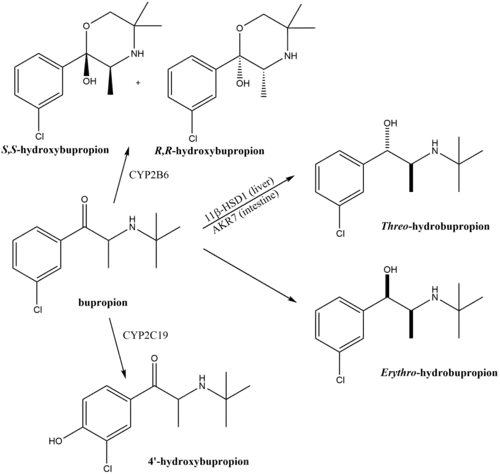

The mechanism of action of bupropion in the treatment of depression and for other indications is unclear.[2] However, it is thought to be related to the fact that bupropion is a norepinephrine–dopamine reuptake inhibitor (NDRI) and negative allosteric modulator of several nicotinic acetylcholine receptors.[2] Bupropion does not act as a norepinephrine–dopamine releasing agent.[128] Pharmacological actions of bupropion, to a substantial degree, are due to its active metabolites hydroxybupropion, threo-hydrobupropion, and erythro-hydrobupropion that are present in the blood plasma at comparable or much higher levels.[2] In fact, bupropion could accurately be conceptualized as a prodrug of these metabolites.[2] Overall action of these metabolites, and particularly one enantiomer S,S-hydroxybupropion, is also characterized by inhibition of norepinephrine and dopamine reuptake and nicotinic inhibition (see the chart on the right).[2] Bupropion has no meaningful direct activity at a variety of receptors, including α- and β-adrenergic, dopamine, serotonin, histamine, and muscarinic acetylcholine receptors.[19]

Bupropion is metabolized in the body by a variety of pathways. The oxidative pathways are by cytochrome P450 isoenzymes CYP2B6 leading to R,R- and S,S-hydroxybupropion and, to a lesser degree, CYP2C19 leading to 4'-hydroxybupropion. The reductive pathways are by 11β-hydroxysteroid dehydrogenase type 1 in the liver and AKR7A2/AKR7A3 in the intestine leading to threo-hydrobupropion and by yet unknown enzyme leading to erythro-hydrobupropion.[2]

The metabolism of bupropion is highly species-dependent.[162][163][164] As an example, oral bupropion results in hydroxybupropion levels that are 16-fold higher than those of bupropion itself in humans, whereas in rats, oral bupropion results in levels of bupropion that are 3.4-fold higher than those of hydroxybupropion.[162] The species-dependent metabolism of bupropion is thought to be involved in species differences in its pharmacodynamic effects.[162][163][164] For example, bupropion produces psychostimulant-like and reinforcing effects in rodents, whereas oral bupropion at therapeutic doses seems to have much less or no potential for such effects in humans.[165]